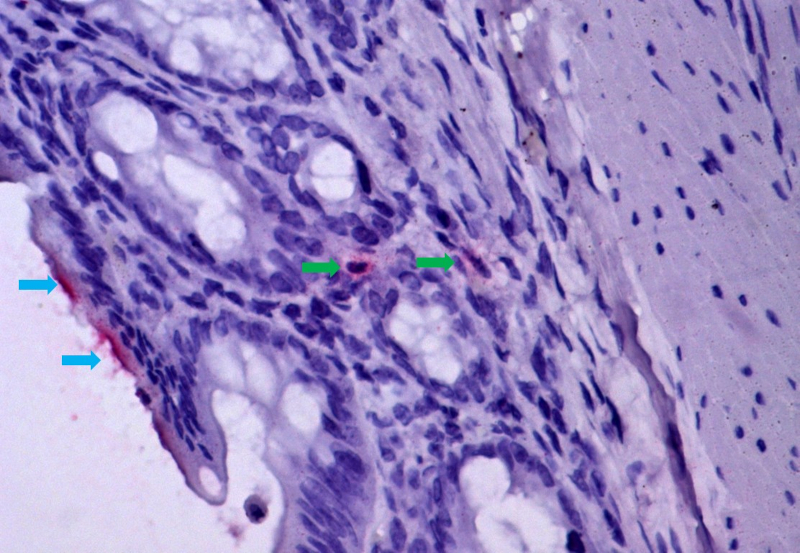

Mucosa intestinal de hamster infectado pelo vírus da febre amarela, demonstrando isquemia e translocação bacteriana, mecanismo de passagem de bactérias e seus produtos (marcados em vermelho, por imunohistoquímica) do lúmen intestinal (setas azuis) para a mucosa intestinal (setas verdes), atingindo a corrente sanguínea. O mesmo mecanismo de lesão ocorre em humanos com febre amarela fatal (imagem: Amaro Nunes Duarte Neto/HC-FM-USP)

“Inicialmente, essas observações foram tratadas como impressões anatômicas do patologista, mas ao analisar as lâminas constatei lesão vascular nos intestinos e no estômago, característica da falta de irrigação. A lesão vascular da mucosa gastrointestinal permite a passagem de bactérias do lúmen intestinal para o sangue e o fígado, agravando o dano inicial pelo vírus da febre amarela e levando ao óbito”, explica Duarte.

Para validar os achados, os pesquisadores da USP associaram-se ao professor Adam Bailey, da Universidade de Wisconsin-Madison, que desenvolveu um modelo experimental de hamster infectado pelo vírus. As análises dos tecidos animais evidenciaram um quadro semelhante ao humano, com hemorragias e trombos na parede intestinal.

“A entrada de bactérias no sangue dos animais mostrou que a translocação é um mecanismo progressivo na evolução da febre amarela grave”, afirma Duarte. Os pesquisadores pretendem agora analisar amostras de pulmões de pacientes fatais para entender os efeitos dessa translocação no órgão.